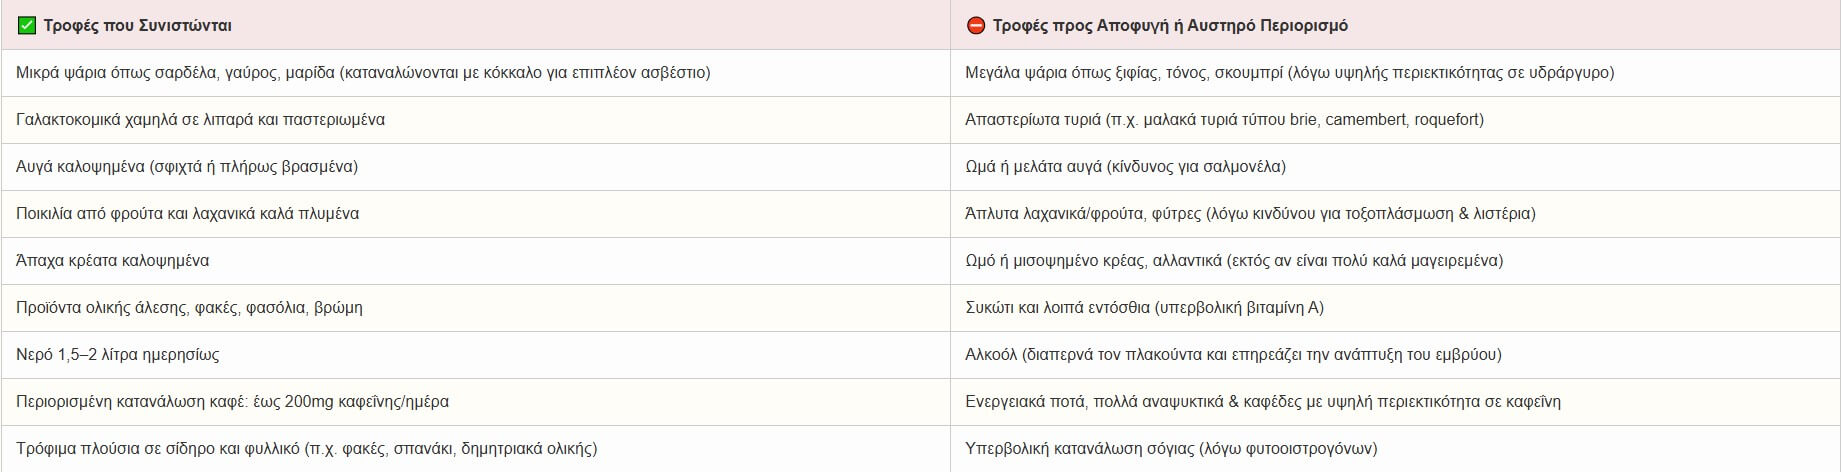

Τι μπορώ να καταναλώνω κατά τη διάρκεια της εγκυμοσύνης – Τι να αποφεύγω;

Η εγκυμοσύνη είναι μια περίοδος αυξημένων διατροφικών απαιτήσεων αλλά και διατροφικής υπευθυνότητας. Η διατροφή της εγκύου επηρεάζει άμεσα τη σωματική και νευροαναπτυξιακή υγεία του εμβρύου. Υπάρχουν τρόφιμα που προάγουν την ανάπτυξη, αλλά και άλλα που μπορεί να ενέχουν κίνδυνο για το έμβρυο ή την μητέρα.

Τρόφιμα προς αποφυγή με περιορισμό

Αλκόολ

o Διαπερνά τον πλακούντα ➝ κίνδυνος για εμβρυϊκό αλκοολικό σύνδρομο (FAS).

o Ακόμη και μικρές ποσότητες μπορεί να επηρεάσουν το ΚΝΣ του εμβρύου.

Μεταβολικά Όργανα (π.χ. συκώτι)

o Πολύ υψηλή περιεκτικότητα σε βιταμίνη Α ➝ πιθανή τερατογένεση στο 1ο τρίμηνο.

o Αντενδείκνυται η συχνή κατανάλωση.

Μεγάλα ψάρια (π.χ. τόνος, ξιφίας, σκουμπρί, ροφός)

o Υψηλά επίπεδα υδραργύρου ➝ νευροαναπτυξιακή τοξικότητα.

o Αντί αυτών, προτιμώνται μικρά ψάρια (σαρδέλες, γαύρος, μαρίδα).

Άψητα/ωμά τρόφιμα ζωικής προέλευσης (ψάρια, αυγά, κρέατα, αλλαντικά)

o Κίνδυνος για Listeria, Salmonella ή Toxoplasma.

o Αποφύγετε sushi, ωμά αυγά, καπνιστά ή μαγειρεμένα ανεπαρκώς τρόφιμα.

Μη παστεριωμένα γαλακτοκομικά

o Πηγή λιστερίωσης ➝ αποβολή ή πρόωρος τοκετός.

Σόγια & προϊόντα της

o Υψηλά φυτοοιστρογόνα ➝ πιθανές ενδοκρινολογικές επιδράσεις (περιορισμός ιδιαίτερα στο 1ο τρίμηνο).

Καφεΐνη

o Μέγιστη συνιστώμενη ποσότητα: 200mg/ημέρα (≈1 φλ. καφές φίλτρου).

o Υπερκατανάλωση ➝ χαμηλό βάρος γέννησης, αυξημένος καρδιακός ρυθμός εμβρύου.

o Προσοχή: βρίσκεται σε καφέ, τσάι, αναψυκτικά, σοκολάτα, ενεργειακά ποτά.

Τρόφιμα που συστήνονται που επιτρέπονται στην εγκυμοσύνη

Μικρά λιπαρά ψάρια (3–4 φορές/εβδομάδα)

o Πηγή ω-3 λιπαρών (EPA/DHA) ➝ συμβάλλουν στη νευροανάπτυξη του εμβρύου.

o Ενισχύουν την πρόληψη της προεκλαμψίας.

Γαλακτοκομικά (παστεριωμένα)

o Πηγή ασβεστίου, πρωτεΐνης και προβιοτικών.

o Προτιμήστε χαμηλά σε λιπαρά προϊόντα.

Αυγά (καλά μαγειρεμένα)

o Πλούσια σε χολίνη και λευκώματα, απαραίτητα για το νευρικό σύστημα.

Πολύχρωμα φρούτα & λαχανικά

o Αντιοξειδωτικά, φυλλικό οξύ, βιταμίνη C ➝ ανοσοπροστασία, αιμοποίηση.

Ολικής άλεσης δημητριακά, όσπρια, καρποί

o Πηγή φυτικών ινών ➝ πρόληψη δυσκοιλιότητας.

o Σταθερή ενέργεια χωρίς απότομες αυξομειώσεις γλυκόζης.

Νερό – Ενυδάτωση

o 2–2.5 λίτρα/ημέρα για επαρκή όγκο αμνιακού υγρού, κυκλοφορία, πέψη.